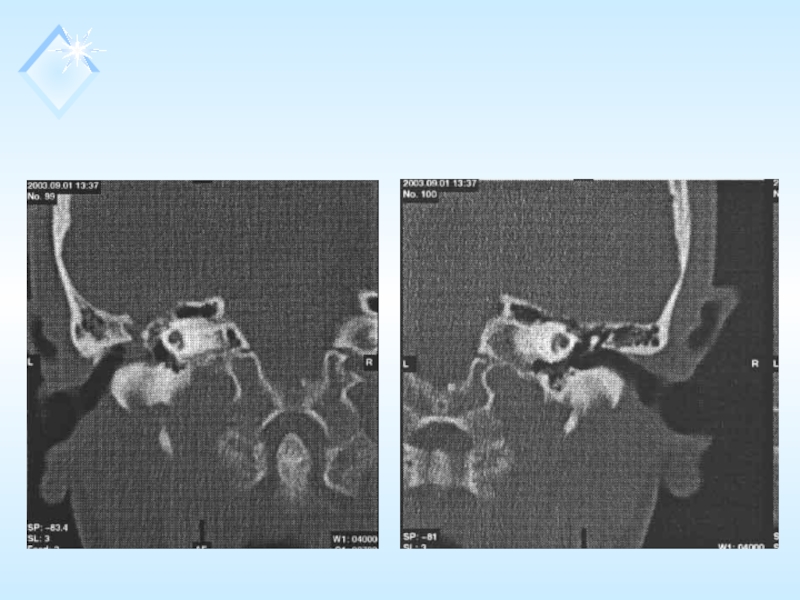

Больной С., 1971 г.р., поступил в ОРВХ 1.09.03 с жалобами

на снижение слуха слева, периодическое истечение жидкости из наружного слухового прохода слева. Из анамнеза выяснено, что заболевание связывает с перенесенной в 1990 г. открытой черепно-мозговой травмой. С 1993 г. отмечает возникновение ликвореи (рецидивы – 3-4 раза в год). По месту жительства получал консервативное лечение. В течении болезни неоднократно исследовалось отделяемое из уха и лабораторно идентифицировано, как спиномозговая жидкость.

На момент осмотра: общее состояние больного удовлетворительное, кожные покровы чистые, обычного цвета. Периферические л/узлы интактны, со стороны внутренних органов на момент осмотра патологии не выявлено.

ЛОР-статус: при передней риноскопии носовая перегородка несколько искривлена вправо, слизистая оболочка полости носа розовая, носовые ходы свободны. Носовое дыхание не затруднено. Орофарингоскопия: зев симметричный, слизистая оболочка розового цвета, влажная, небные миндалины без патологического содержимого в лакунах.

Отоскопия:

AD – наружный слуховой проход широкий, свободный, б/п серая, целая, контурирует.

AS - наружный слуховой проход широкий, свободный, дефект костного кольца барабанной перепонки и перфорация, в верхне-заднем квадранте.